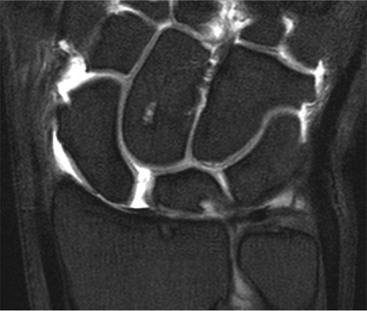

Abnormal communication between the radiocarpal and midcarpal joints may be seen on arthrography (Fig. 46-28), which is usually combined with MRI or CT16 (Figs. 46-29 and 46-30). However, direct visualisation of the ligaments is possible with conventional MRI. The most important features to describe that help determine management include the following: